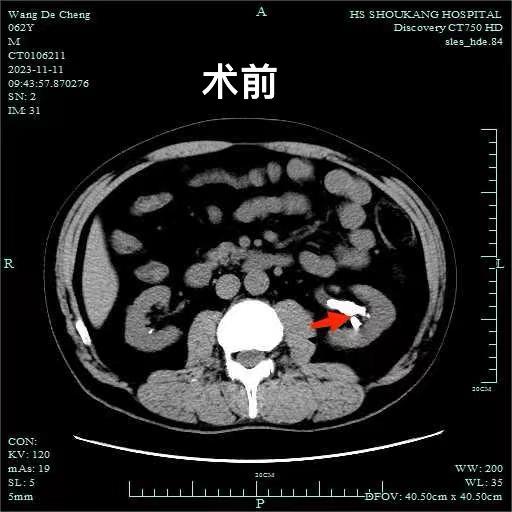

▲术前VS术后

术后王某恢复良好,复查腹部CT未见结石残留,很快便出院了。王某与家属对治疗效果非常满意。